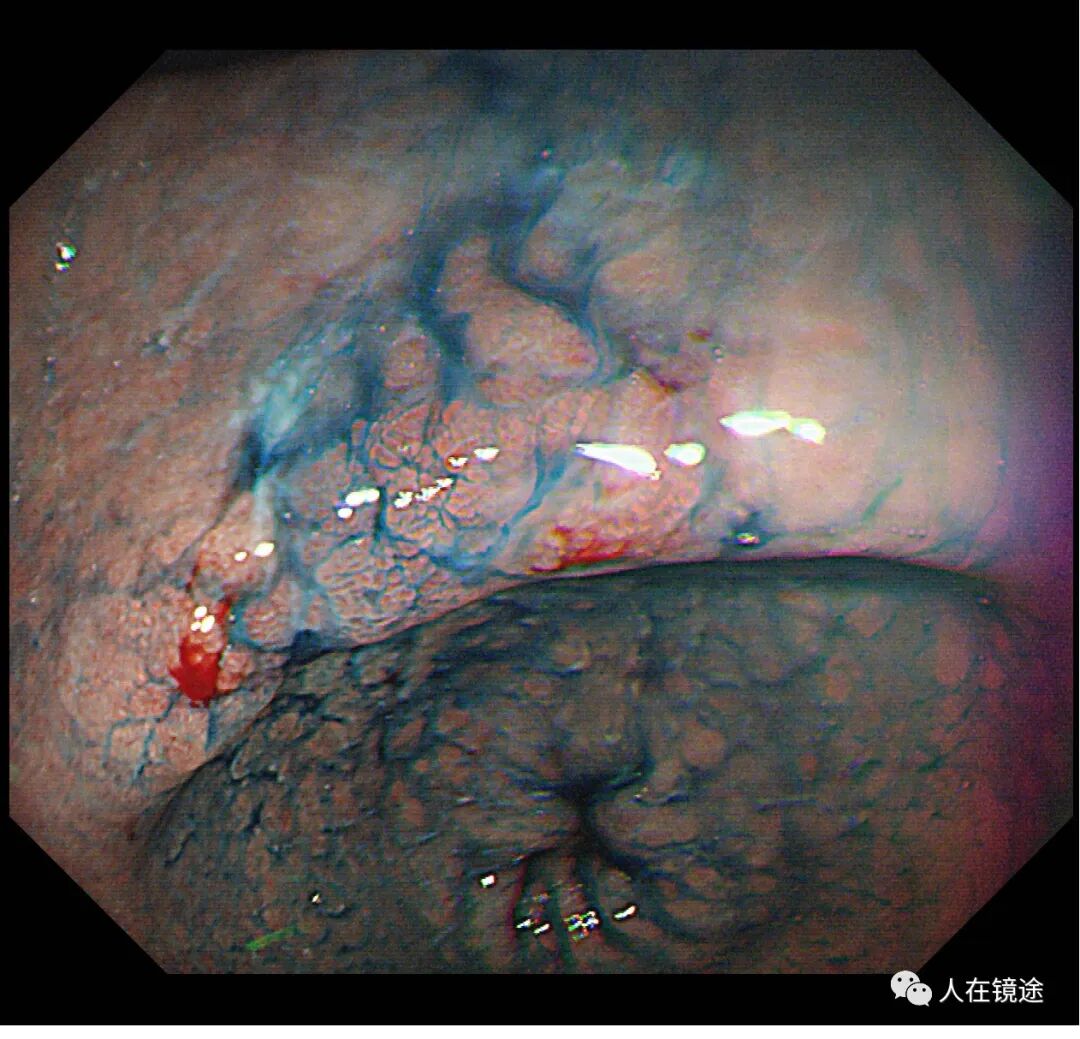

靛胭脂染色示:病变边界清楚,约0.8*1.2cm大小,表面粘膜高低不平,微结构紊乱伴自发性出血。

NBI+靛胭脂+近焦示:病变边界清楚,约0.8*1.2cm大小,表面粘膜高低不平,微结构紊乱伴自发性出血